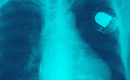

De acordo com os autos do processo n° 0036775-56.2013.8.08.0035, o usuário do plano contratado procurou a instituição para a realização de cirgurgia de implante de marcapasso bicameral, mas recebeu resposta negativa, com a justificativa de que não havia, no Estado do Espírito Santo, médicos credenciados ao plano para realizar o procedimento.